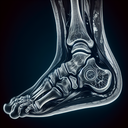

МРТ гомілково-ступневогу суглобу

МРТ гомілково-ступневого суглобу використовується для детальної оцінки його структур. Це дослідження може бути рекомендоване в наступних випадках: 1. **Травми**: Підозра на пошкодження зв'язок, сухожиль, хрящів або м'язів після розтягнень чи вивихів...